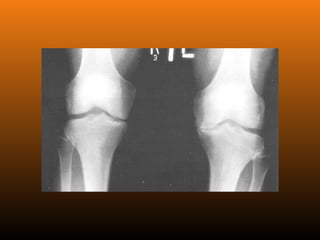

RADIOLOGIA

No início da doença não se observam anormalidades. Com seu

desenvolvimento, observam-se:

 Diminuição do espaço intra-articular

 Esclerose subcondral (eburnação)

 Osteófitos;

 Erosão e anquilose óssea (pseudocistos ósseos).

PATOLOGIA As alterações patológicaspresentes nas articulações com osteoartrite incluem a degradação da cartilagem articular, o espessamento do osso subcondral, a formação de osteófitos, graus variáveis de inflamação sinovial, degeneração de ligamentos no joelho, meniscos e hipertrofia da cápsula articular.